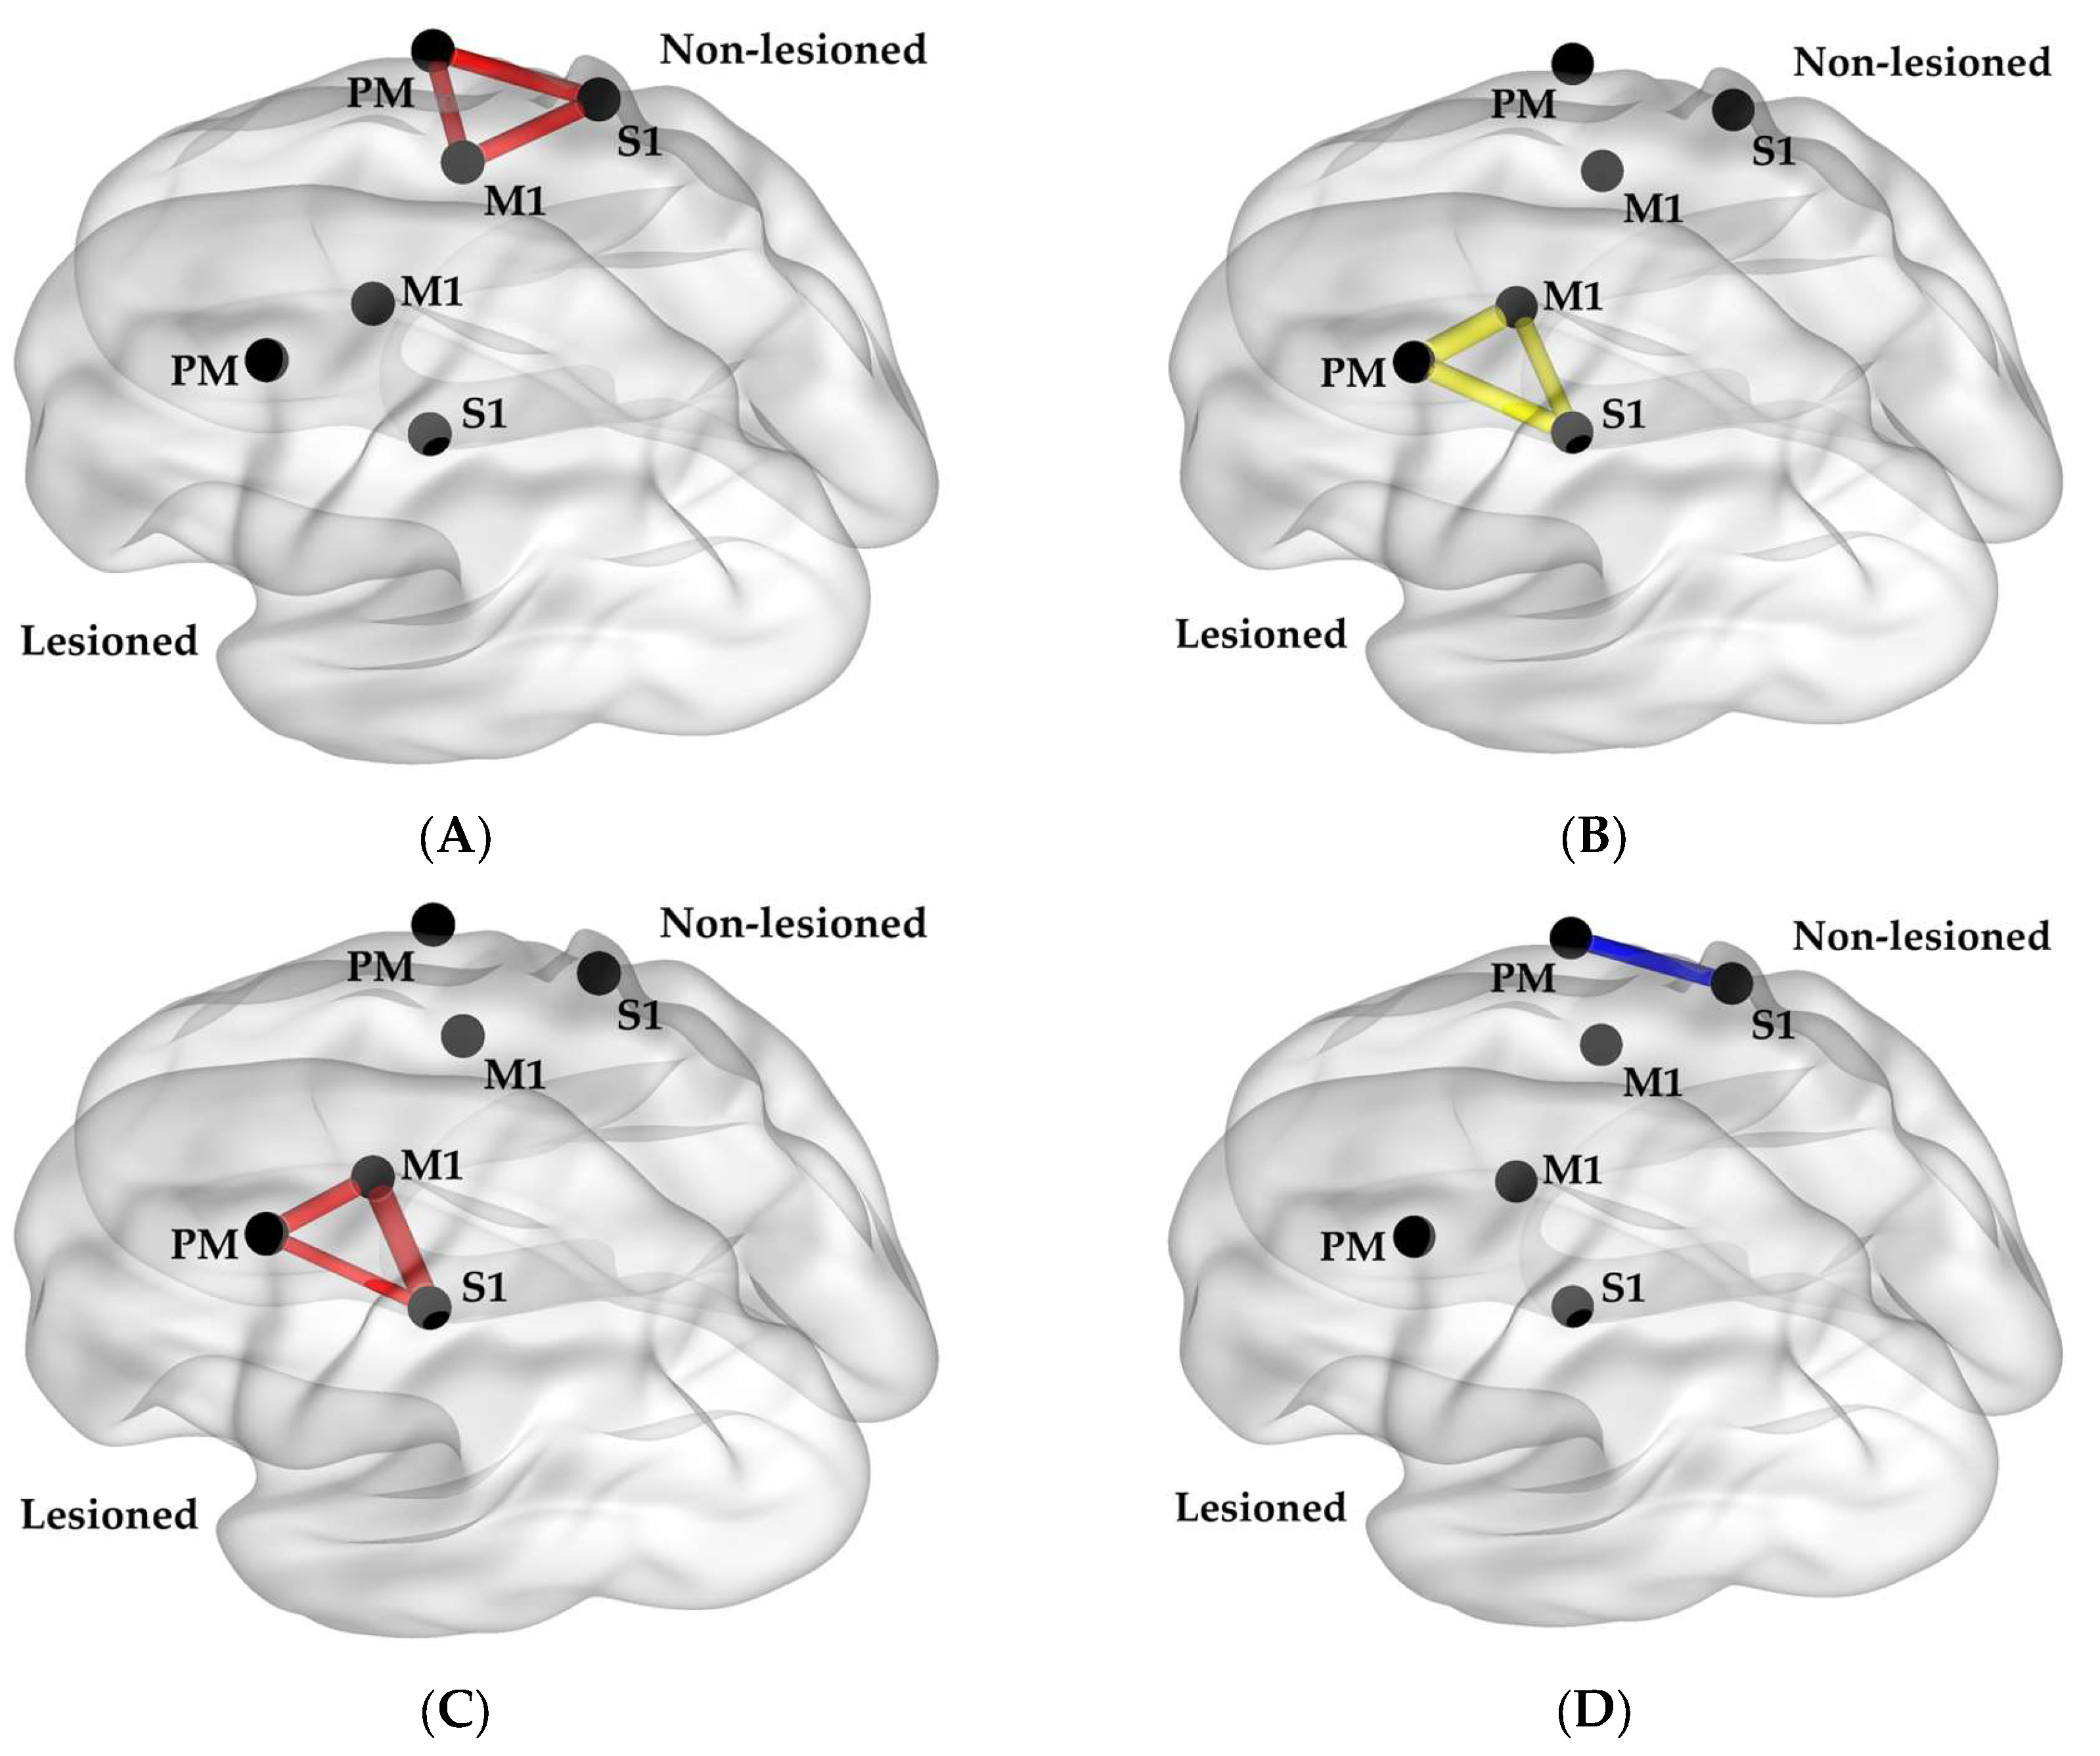

3.2. Relationship between Grip Measures and Functional Neural Connectivity

4. Discussion

4.1. Overall Findings

4.2. Connectivity and Sensorimotor Function